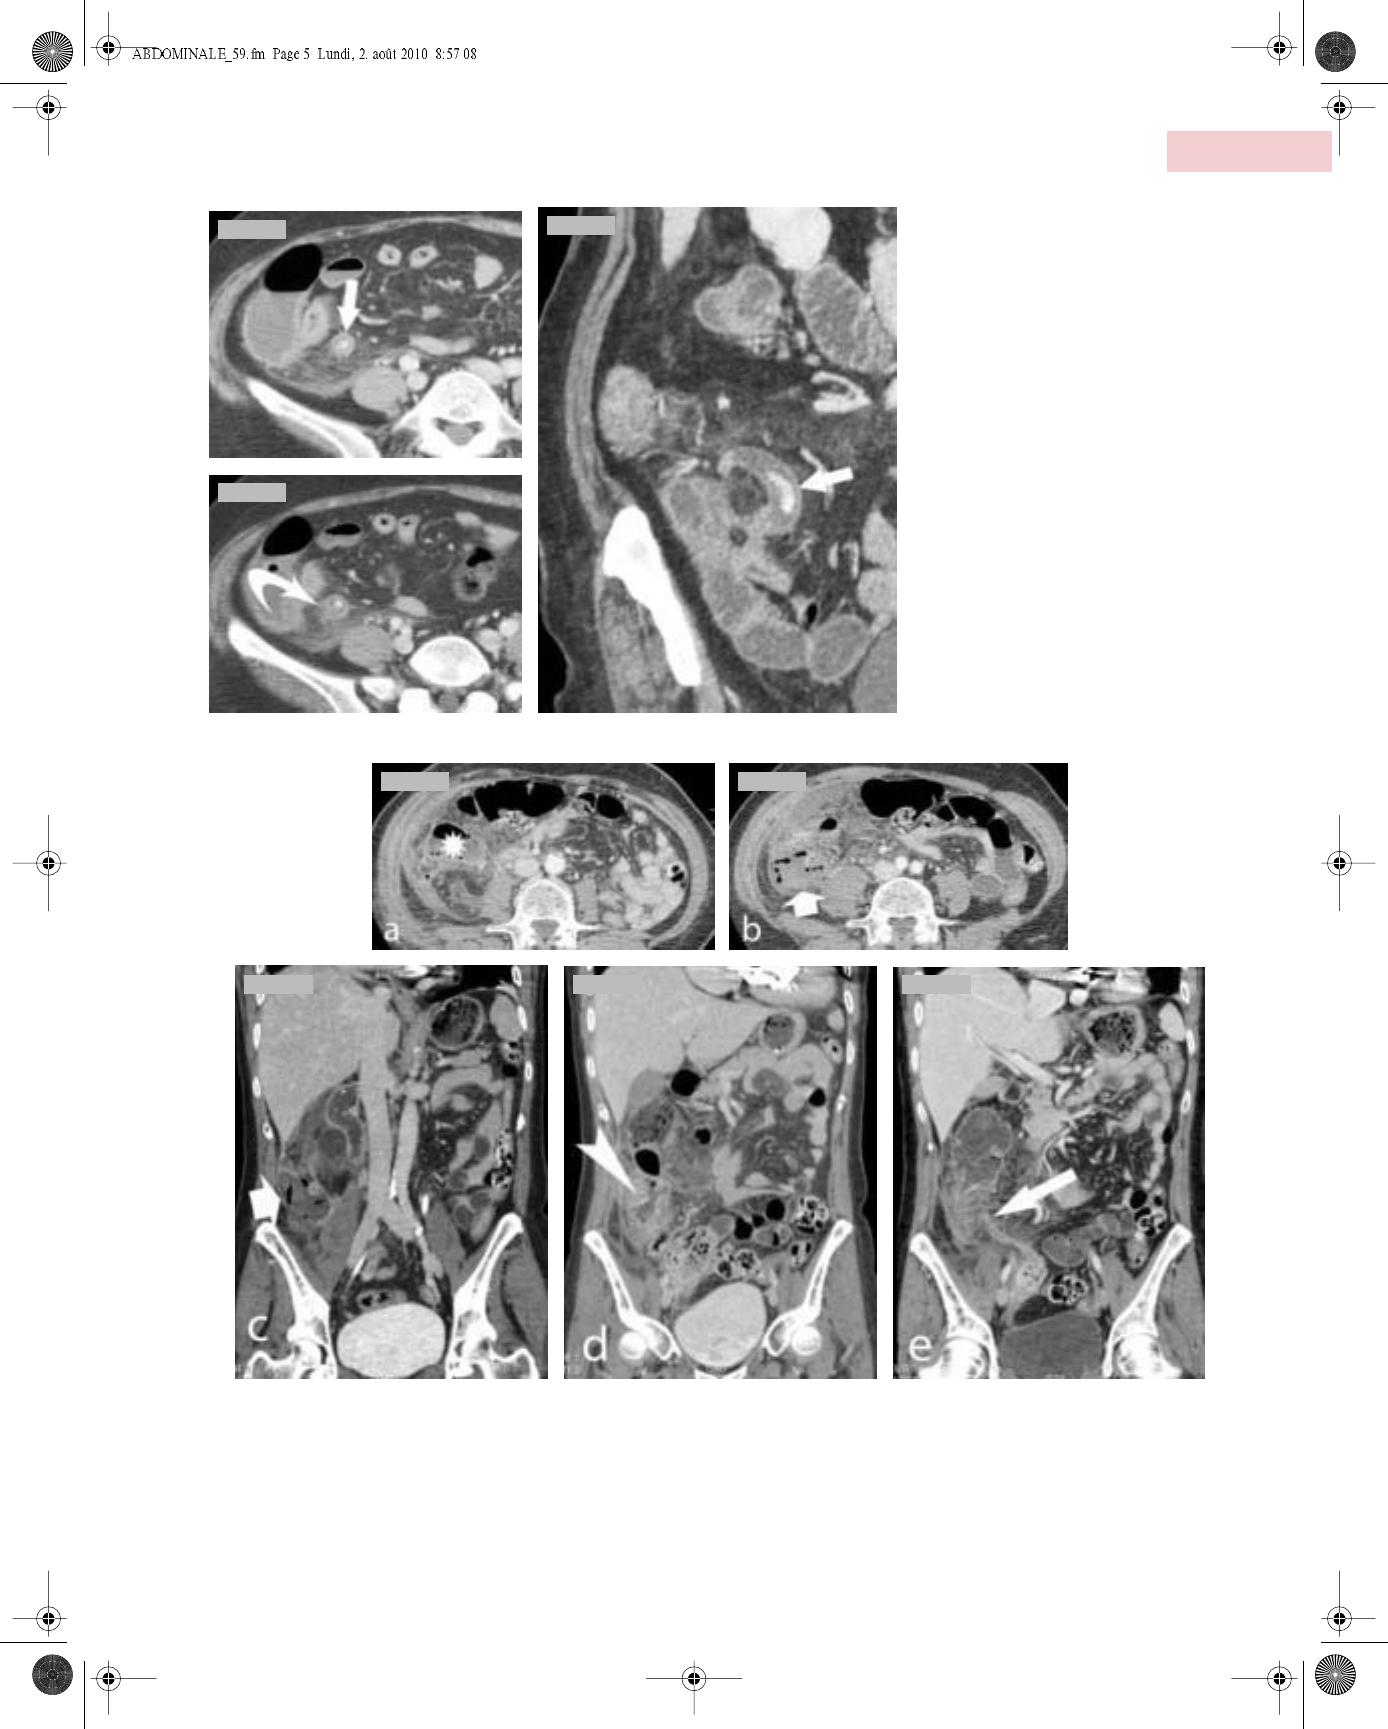

Il faut donc toujours débuter l’analyse échographique ou tomo-

densitométrique par la recherche de la position du cæcum (ortho-

ou hétérotopique) pour suivre ensuite le trajet appendiculaire.